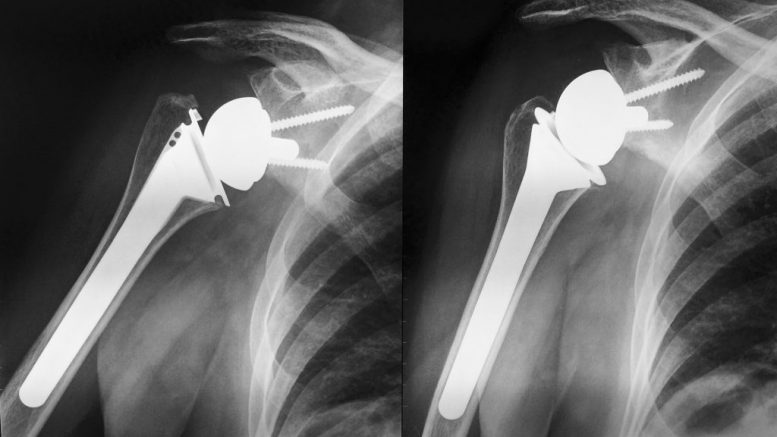

È in aumento in Italia il numero delle persone che hanno necessità di impiantare una protesi di spalla per eliminare il dolore e migliorare i movimenti per cercare di rispondere alle esigenze di questi pazienti e per un proficuo aggiornamento su metodiche e materiali, il dottor Ariberto Di Felice, responsabile dell’ortopedia della Casa di cura Pierangeli di Pescara, ha stato organizzato il convegno “Il ruolo della protesi di spalla, problematiche e soluzioni oggi”. La due giorni, che si è svolta a Città Sant’Angelo, ha messo a confronto specialisti del comparto privato, pubblico e universitario di diverse realtà italiane.